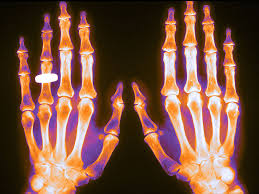

Pérdida ósea en pacientes con enfermedad musculoesquelética reumática inflamatoria tratados con dosis bajas de glucocorticoides y prevención con medicamentos contra la osteoporosis

Las dosis de glucocorticoides tan bajas como 2,5 mg/día se asociaron con la pérdida de densidad mineral ósea (DMO) en pacientes con enfermedades musculoesqueléticas reumáticas inflamatorias (EMRi), pero este efecto se pudo prevenir. La pérdida de DMO en pacientes que recibieron ≥5 mg/día no se previno por completo con los medicamentos contra la osteoporosis que se usan actualmente en la práctica clínica, lo que resultó en un mayor riesgo de fractura. Arthritis Rheumatol, 24 de abril de 2023